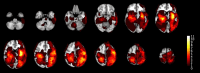

Methods: Using a simulation approach, we analyzed magnetic resonance imaging (MRI) scans of stroke-suspected patients within 4.5 h of symptom onset to assess TCCS and NIRS for identifying imaging-based IVT contraindications. Our study included both primary and sensitivity analyses, each employing conservative and optimistic scenarios. The primary analysis integrated clinical information from the emergency department, while the sensitivity analysis evaluated overall performance across all patients, regardless of clinical information. The conservative scenario defined TCCS detecting acute deep-brain hemorrhages or tumors >20 mm from scalp surface or > 10 mL in volume or causing >4 mm midline-shift, while NIRS was defined detecting them <20 mm from scalp surface with a volume > 3.5 mL. The optimistic scenario defined TCCS detecting intracranial or subarachnoid acute/subacute hematoma or tumors >20 mm from scalp surface or > 5 mL in volume or causing >2 mm midline-shift, while NIRS was defined detecting them <35 mm from the scalp surface with volume > 3.5 mL.

Results: We assessed 1,089 consecutive patients undergoing acute MRI, identifying 69 with imaging-based IVT contraindications, of which 40 had additional non-imaging contraindications. In the primary analysis, among those 29 patients without non-imaging-based contraindications, TCCS/NIRS would have detected 15 of 25 ICH and 3 of 4 malignant tumors in the conservative scenario. In the optimistic scenario, 18 of 25 ICH and all malignant tumors would have been detected. In the sensitivity analyses, the conservative scenario would have detected 30 of 52 ICH and 8 of 17 malignant tumors, while the optimistic scenario would have identified 37 of 52 ICH and 12 of 17 malignant tumors.